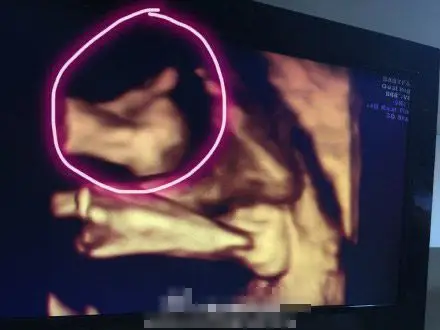

林志颖晒双胞胎儿子b超照 弟弟孕肚中比赞_滚动新闻_烟台大众网